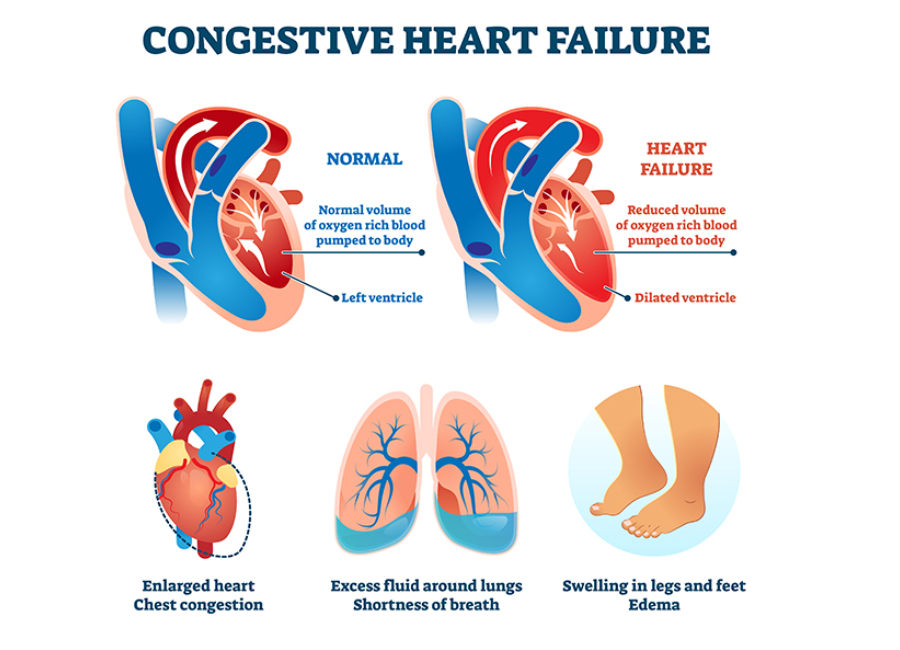

Congestive Heart Failure Symptoms In Dogs

Is Congestive Heart Failure In Dogs Fatal

What Is Congestive Heart Failure In Dogs

What Is Congestive Heart Failure In Dogs